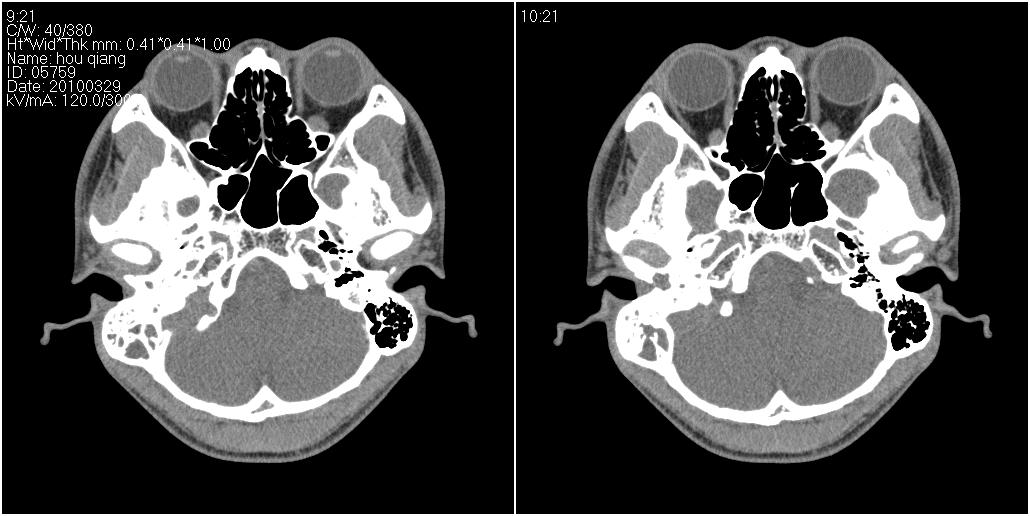

标题: CT25419:男性,18岁。右耳肿、痛5个多月。 [打印本页]

标题: CT25419:男性,18岁。右耳肿、痛5个多月。

右侧中耳乳突炎累及外耳道,鼻咽腺样体肥大。

1)右侧慢性中耳乳突炎并右侧中耳腔及外耳道肉芽肿或胆脂瘤形成。2)鼻咽腺样体肥大。